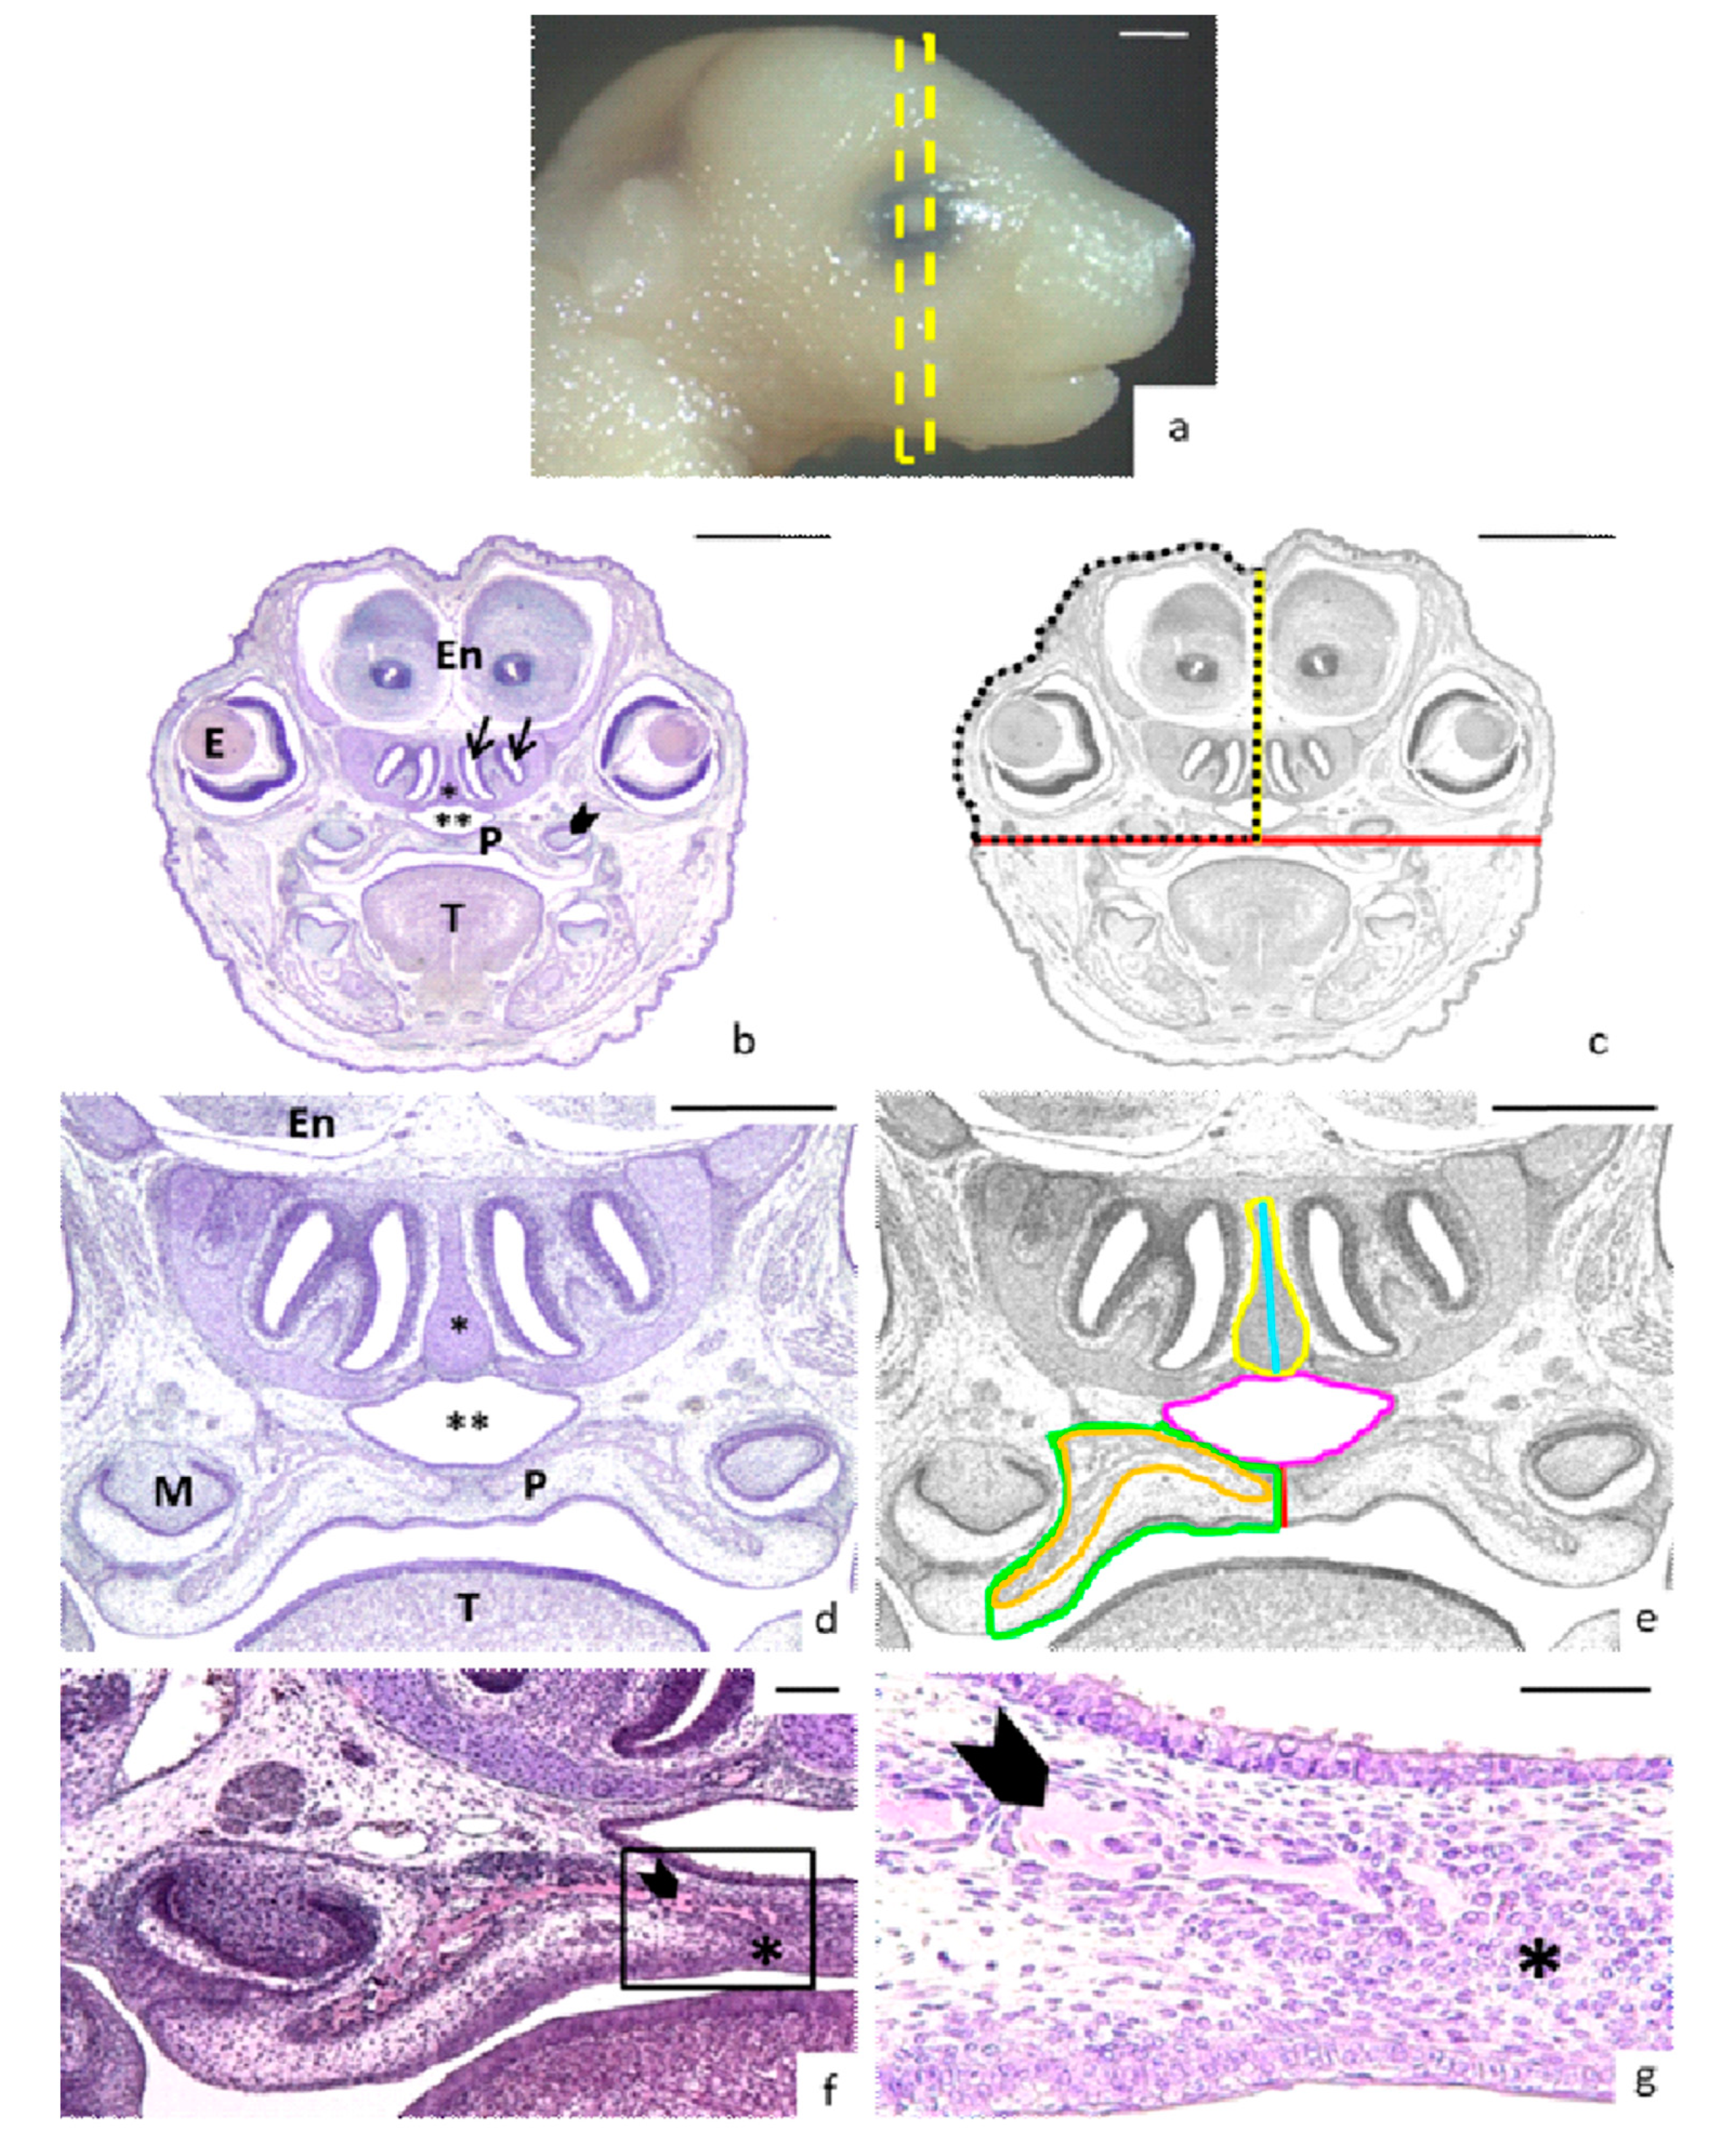

For head measures, sections were chosen where the developing molar, eyes, and two nasal conchae were visible (Figure 1a–b). The width of the head was obtained drawing a horizontal line on the upper point of the palate vault connecting the developing molars (Figure 1b–c). The head height was obtained drawing a vertical line from the middle of the palate to the top of the head passing between olfactory bulbs of the encephalon (Figure 1c). The half head area comprised the surface between these horizontal and vertical lines and another which followed the external surface of the head (Figure 1c). To study the asymmetry of the head, the surface of the right side was compared with that of the left side. The total head area was obtained by adding the right and left areas.

Figure 1.

Head and nasopalatine region measurements. (a) Lateral view of a control head E17-fetus. The yellow rectangle crossing the eye indicates the block of sections selected for measurements. (b) Coronal section showing the landmarks for measurements: The nasal meatus (arrows), the eyes (E) and the developing molars (arrows heads) (En: encephalon; P: palate; T: tongue; asterisk: nasal septum; double asterisk: nasopharynx). (c) Description of head measurements on the same black and white image: width (red line), height from palate to top of the head (yellow line) and area of the half head (discontinuous black line). (d) Magnification of the nasopalatine region (T: tongue; P: palate; M: developing molar; double asterisk: nasopharynx; asterisk: nasal septum; En: encephalon). (e) Description of nasopalatine region measurements on the same black and white image: thick of the palate (red line); area of the half of the palate (green line); area of the bone tissue inside the palate area (orange line), area of the nasopharynx (pink line), area (yellow line) and height (blue line) of the nasal septum. (f) Magnification of the right half palate: bone tissue (arrowhead) and the osteogenic condensation (asterisk). (g) Magnification of the rectangle marked in (f): bone tissue (arrowhead) and the osteogenic condensation (asterisk). Scale bars: (a–c) 1 mm; (d–e) 500 µm; (f) 100 µm; (g) 50 µm.

For the measurement of the thick of the palate, a vertical line was drawn in the middle of the palate (Figure 1d–e). In cases of cleft palate, the thickness was registered as 0 µm. For the measurement of palate area, the lower limit was the oral epithelium until the developing molar, the external limit was the border between the developing molar and the inner bone until the corner of nasopharynx, continuing the nasopharyngeal epithelium superiorly until the internal limit (Figure 1e). The right and left measured areas were added together to obtain the palate total area.

The bone tissue surface was measured inside the palate area because the formed bone was distinguishable from the osteogenic condensation, which was a mesenchymal cell condensation before osteogenesis. The bone tissue resembled a pink-stained sea sponge, while the mesenchymal cells appeared condensed around it with the nuclei very close and was stained purple (Figure 1f–g). In some cases, the bone tissue cells appeared separated into islands or aggregates (Figure 1f–g) which were measured and added to obtain total bone tissue area on each side. The total bone area was obtained by adding its right and left areas.

The nasopharynx was an air passage over the palate, whose area was also measured (Figure 1d–e). The nasal septum area and height, which is located above the nasopharynx, was also measured (Figure 1d–e).